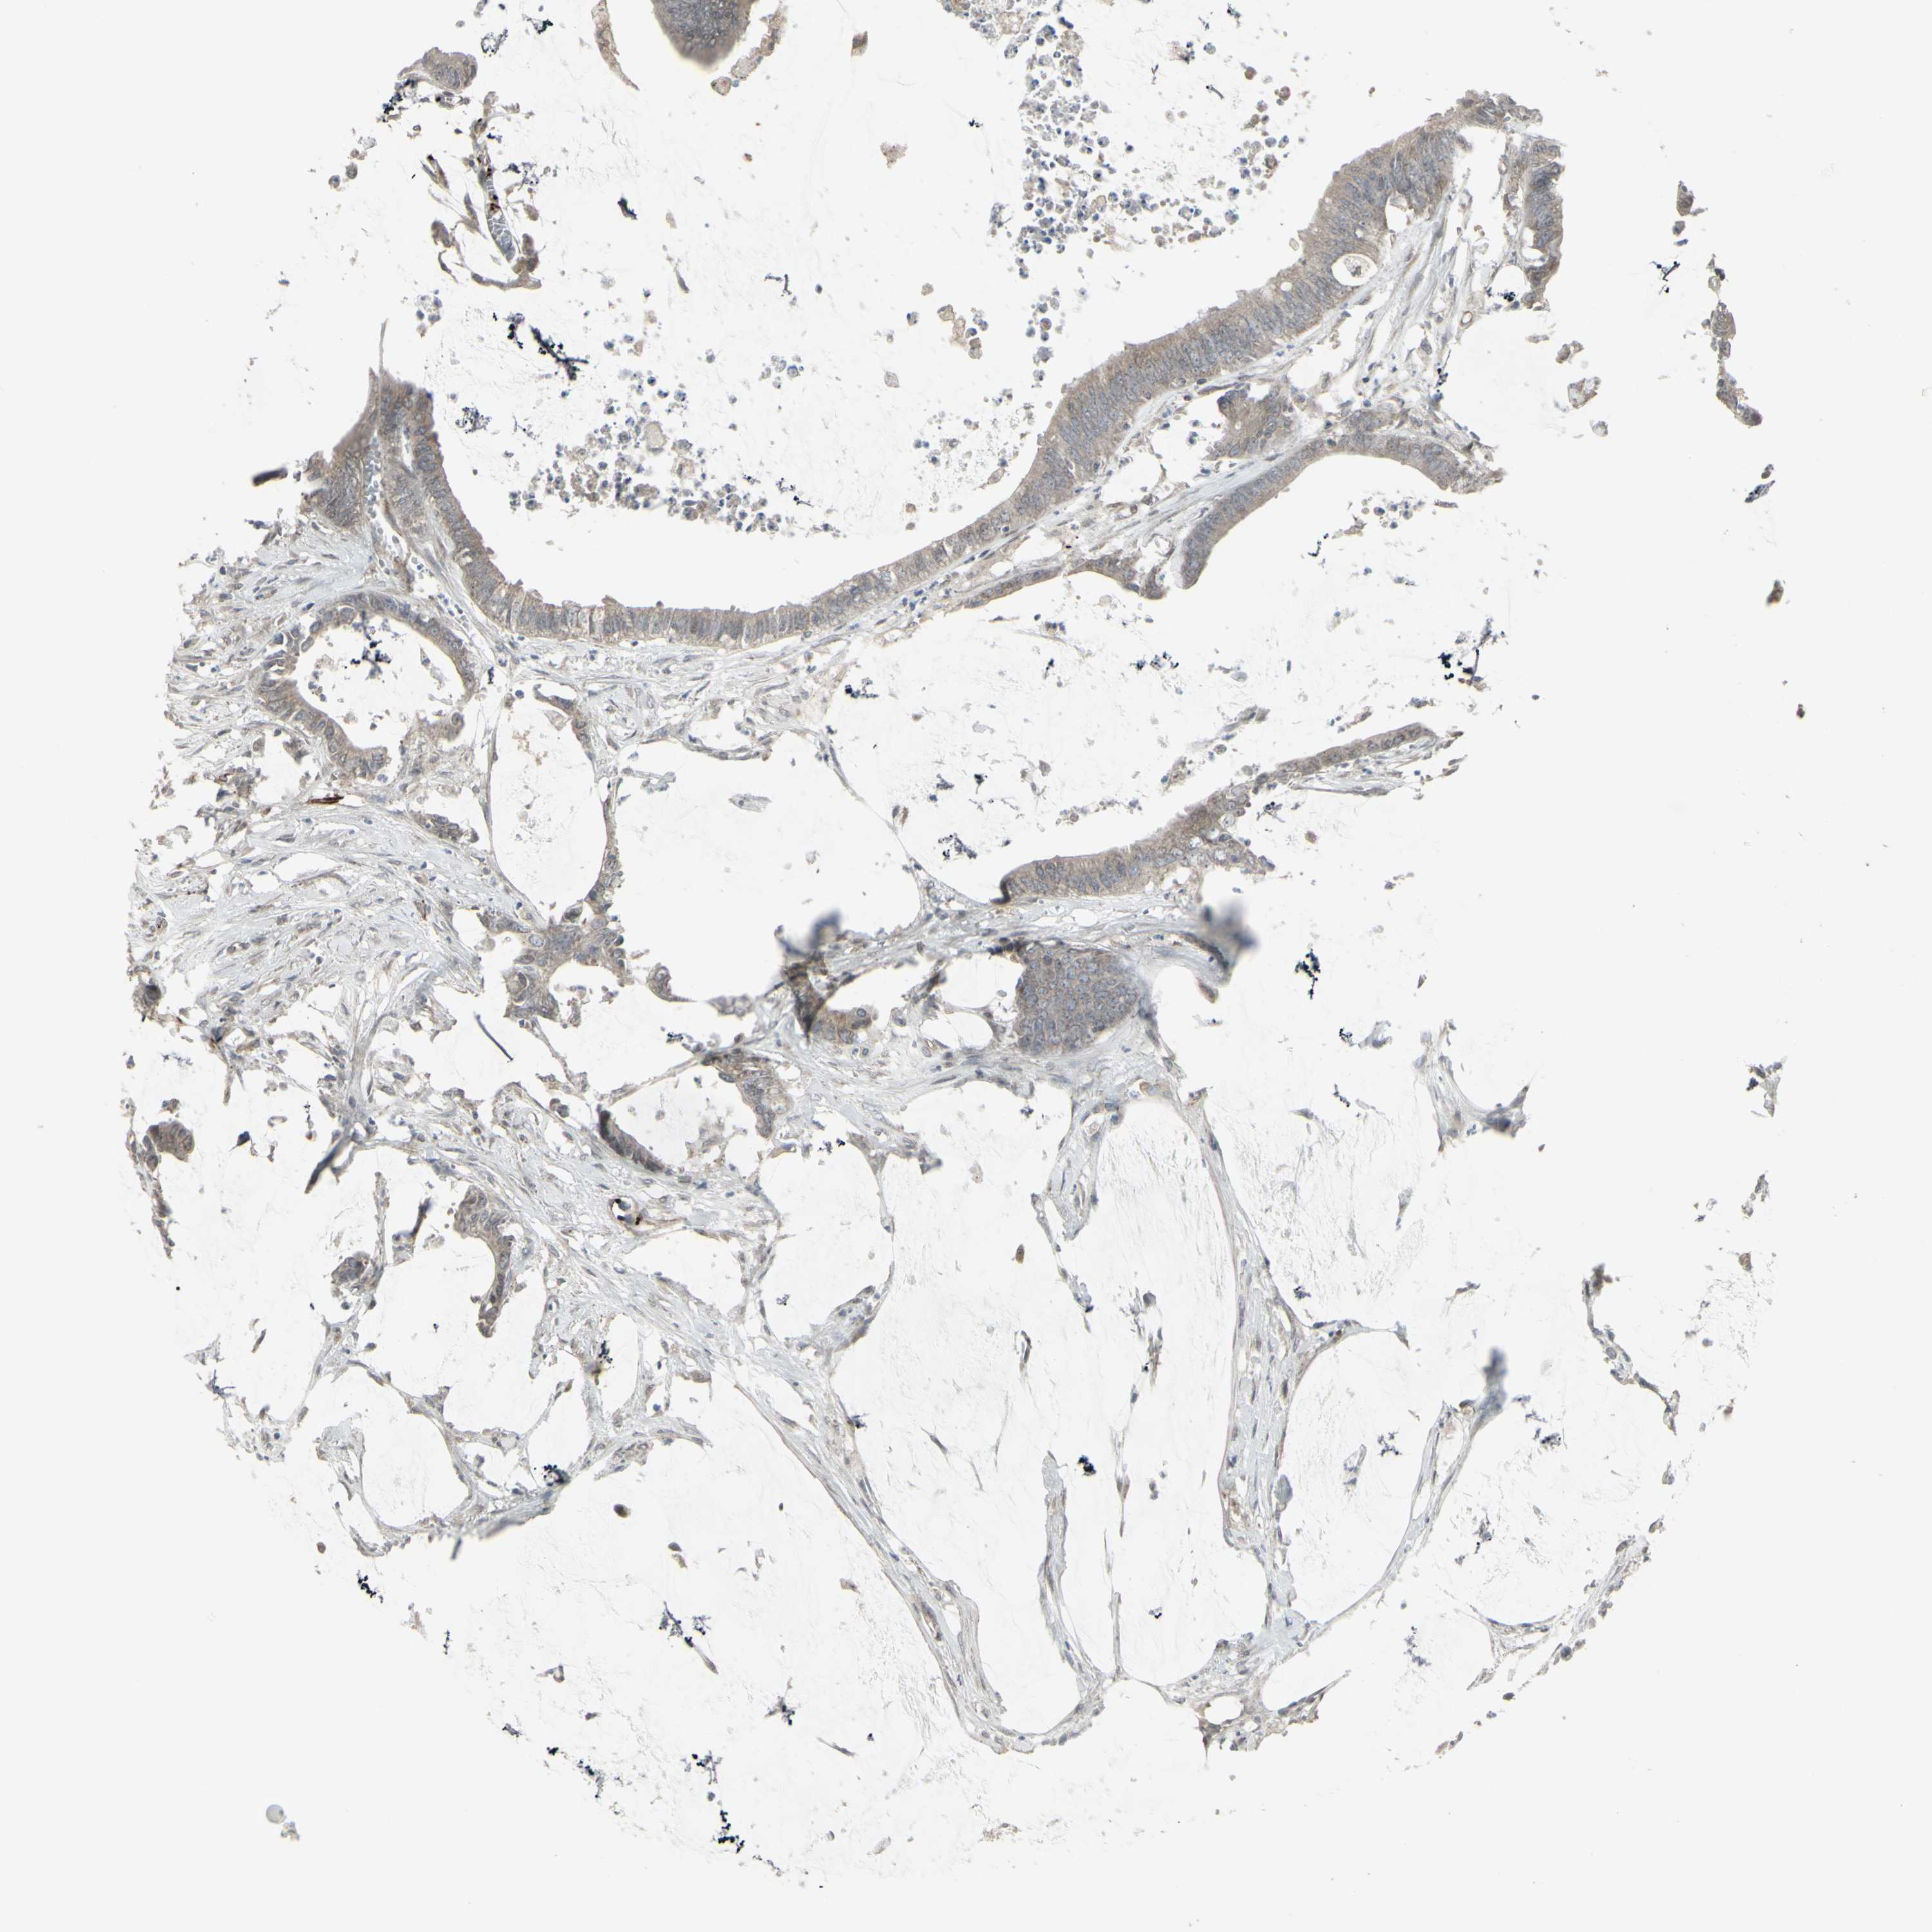

RECTUM ADENOCARCINOMA (TCGA) - Interactive survival scatter ploti

DTX3L is not prognostic in Rectum Adenocarcinoma (TCGA)

Average pTPM 24.1

Number of samples 88